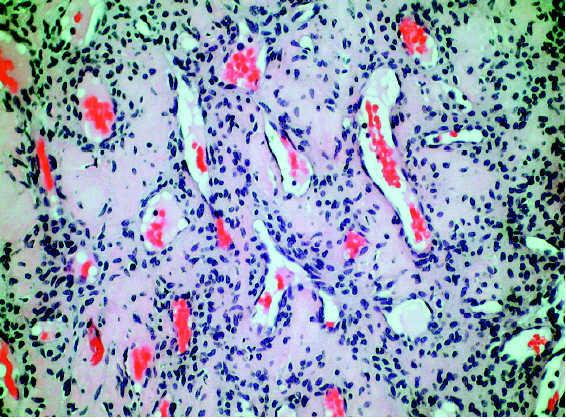

El examen histopatológico evidenció un tumor no encapsulado localizado en la dermis, compuesto por numerosas luces vasculares dilatadas con hematíes en su interior, rodeadas por células endoteliales y pequeños agregados de células glómicas (fig. 2). Desde el punto de vista inmunohistoquímico las células glómicas expresaron actina muscular específica y vimentina, pero la desmina resultó negativa. No se descubrieron antecedentes familiares de lesiones similares.

Fig. 2.--En la dermis, luces vasculares con hematíes en su interior rodeadas de células endoteliales y varias capas de células glómicas. (Hematoxilina-eosina, ×200.)